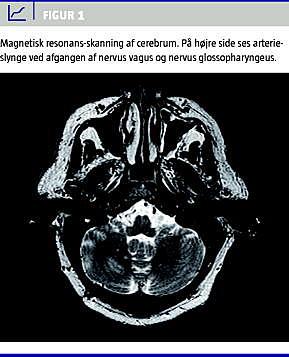

Effekten holdt indtil sommeren 2007, hvorefter patientens glossofaryngeusneuralgi recidiverede. Smerteanfaldende tiltog i hyppighed og intensitet. De kardielle symptomer opstod primo oktober 2007, i begyndelsen i form af svimmelhed og nærsynkoper. Symptomerne udviklede sig i løbet af et par uger til at være egentlige synkoper, der altid forekom i tilslutning til smerteanfald. Episoderne varede under et minut. Der blev observeret bradykardi med puls ned til 20-25 slag/minut og systolisk blodtryk ned til 50 mmHg. Patientens elektrokardiogram under anfald viste sinusbradykardi og sinusarrest med nodal eskapaderytme. Isoprenalininfusion var uden effekt. En ny MR-skanning af cerebrum med angiosekvenser viste højresidig vaskulær kontakt til nervus glossopharyngeus. Patienten blev reopereret under beredskab med zollpacemaker via retrosigmoidal adgang. Man fandt en stor arterieslynge, som komprimerede nervus vagus og nervus glossopharyngei. Nerverne blev fridissikeret og holdt adskilt fra karret med en mèche (polytetrafluoroethylen felt ) (Figur 1 ).